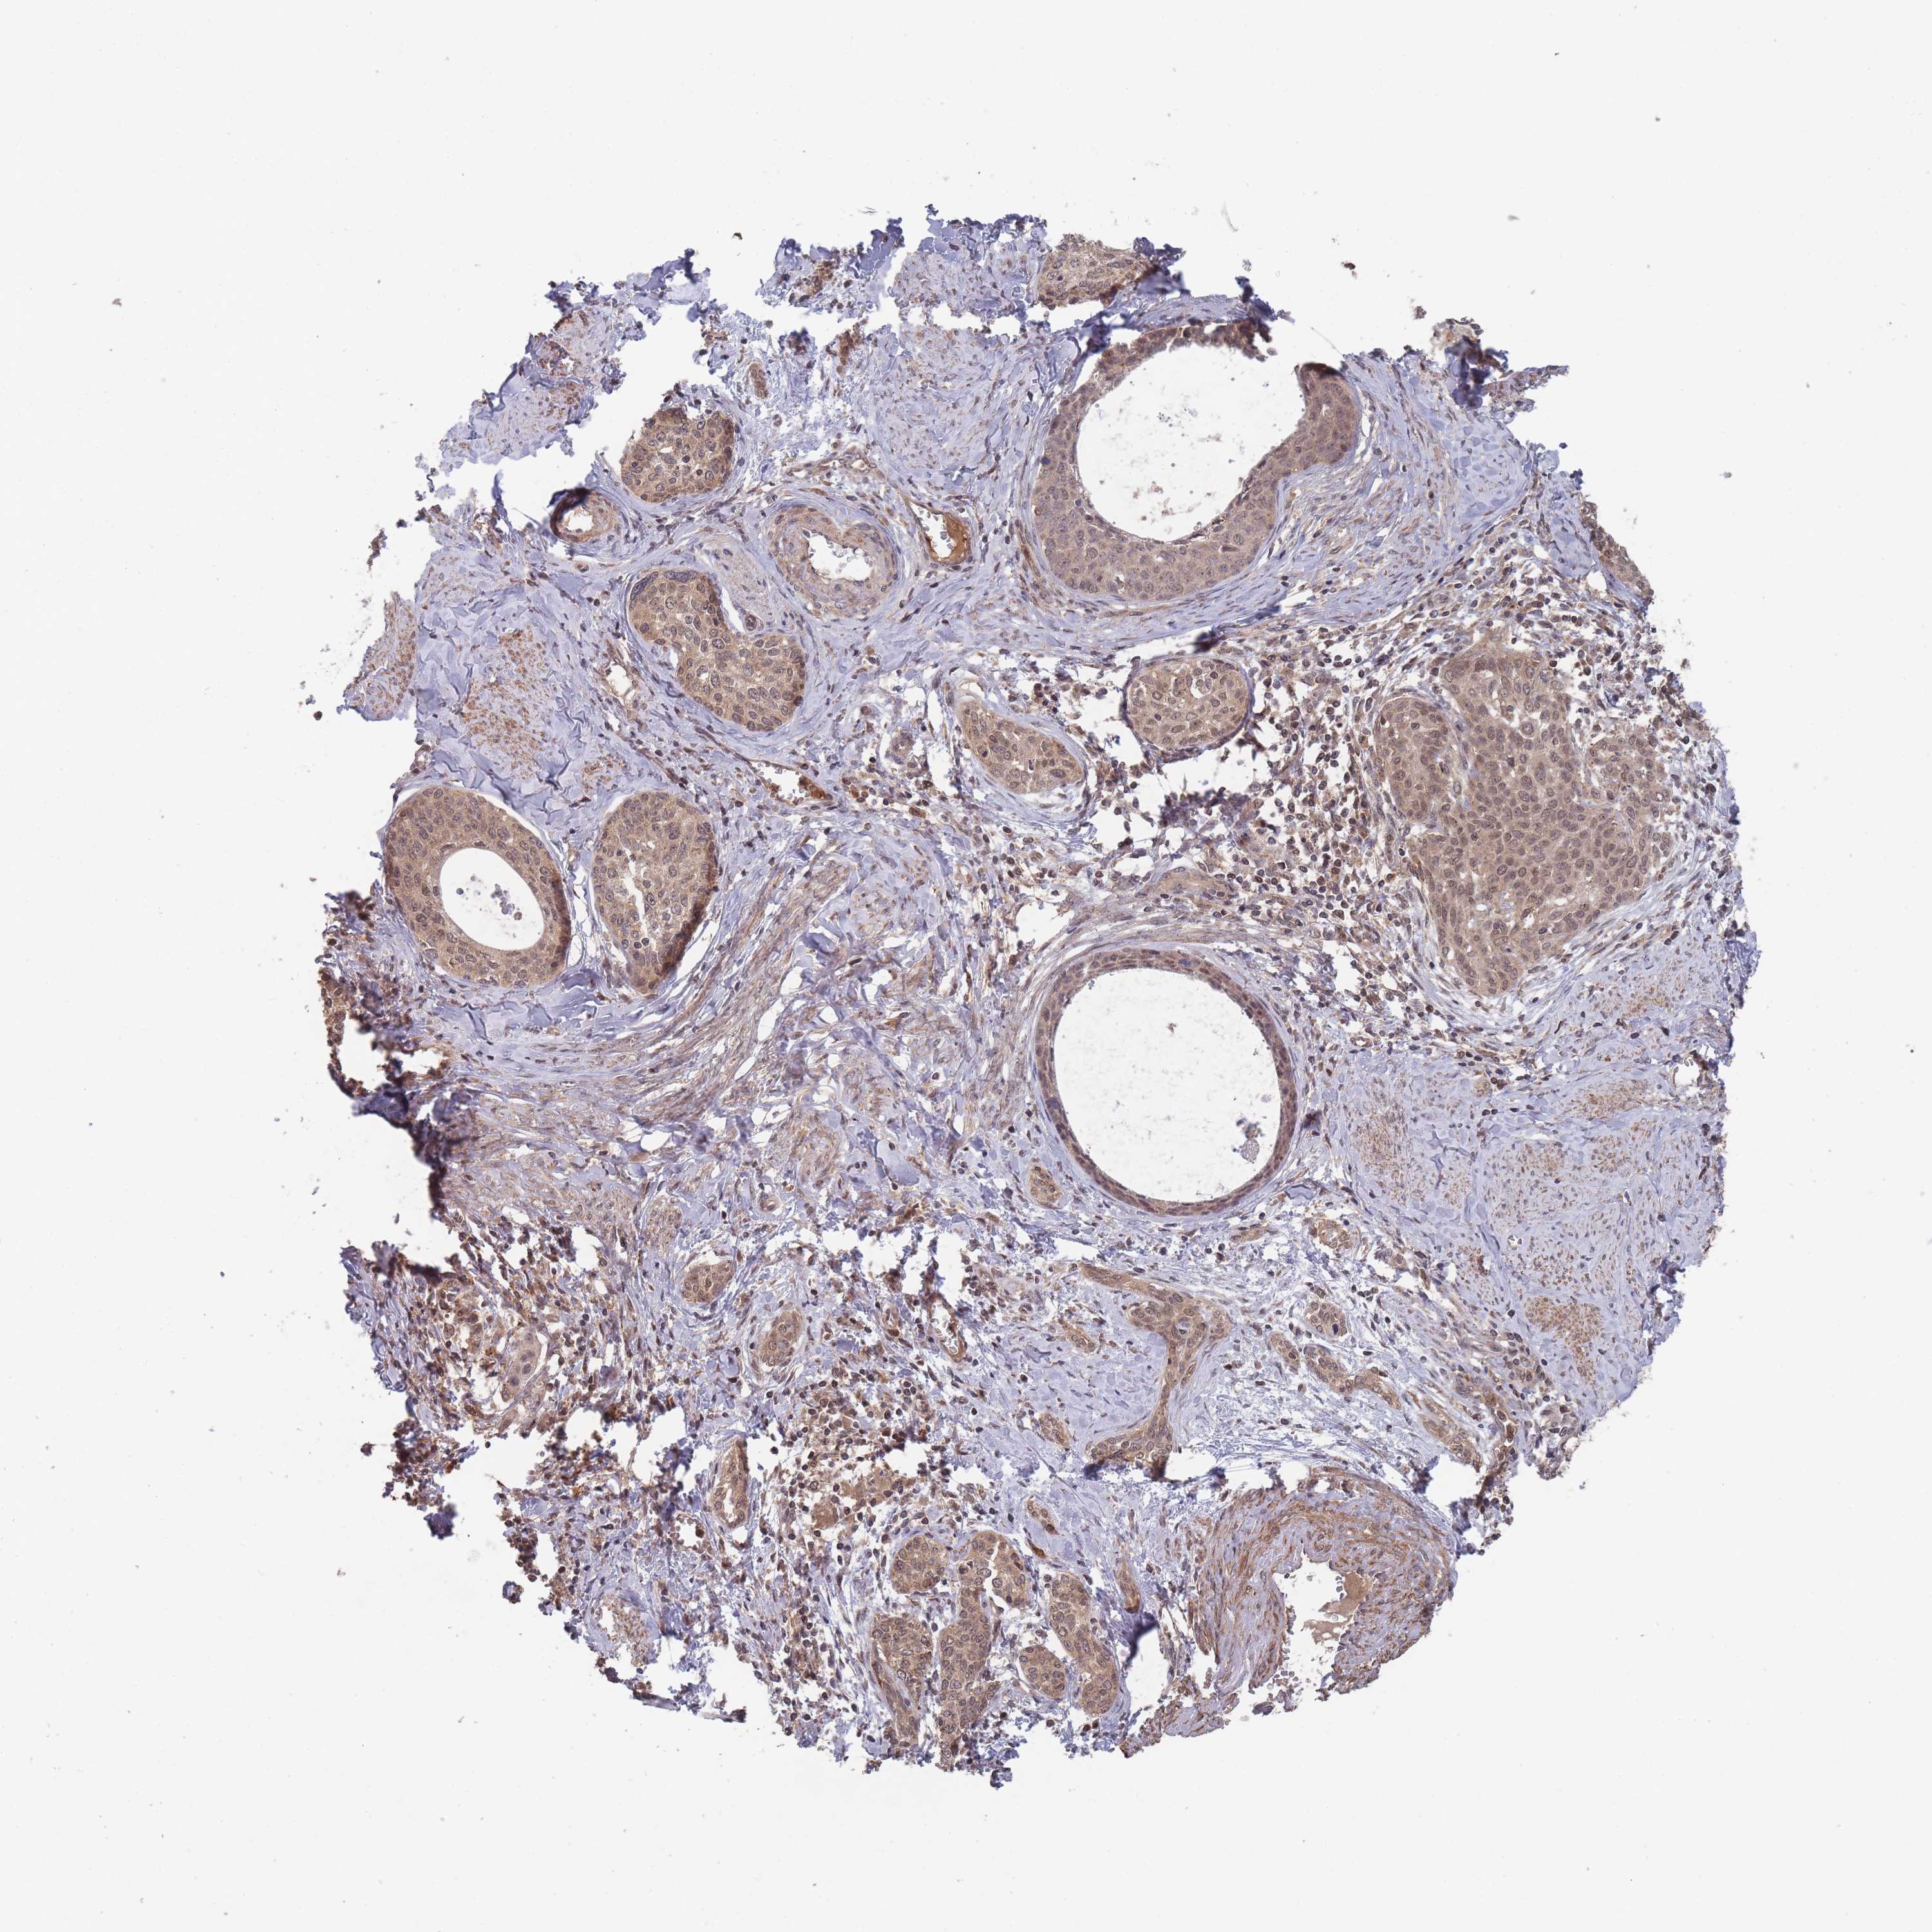

CERVICAL CANCER - Protein expressioni

A mouse-over function shows sample information and annotation data. Click on an image to view it in a full screen mode. Samples can be filtered based on level of antibody staining by selecting one or several of the following categories: high, medium, low and not detected. The assay and annotation is described here.

Note that samples used for immunohistochemistry by the Human Protein Atlas do not correspond to samples in the TCGA dataset.

Antibody stainingi

Antibody staining in the annotated cell types in the current human tissue is reported as not detected, low, medium, or high, based on conventional immunohistochemistry profiling in selected tissues. This score is based on the combination of the staining intensity and fraction of stained cells.

Each image is clickable and will lead to virtual microscopy that enables deeper exploration of all samples and also displays staining intensity scores, fraction scores and subcellular localization as well as patient and tissue information for each sample.

Antibody HPA050275

Staining

High

Medium

Low

Not detected

Intensity

Strong

Moderate

Weak

Negative

Quantity

>75%

75%-25%

<25%

None

Location

Nuclear

Cytoplasmic/membranous

Cytoplasmic/membranous,nuclear

Squamous cell carcinoma, NOS

Adenocarcinoma, NOS